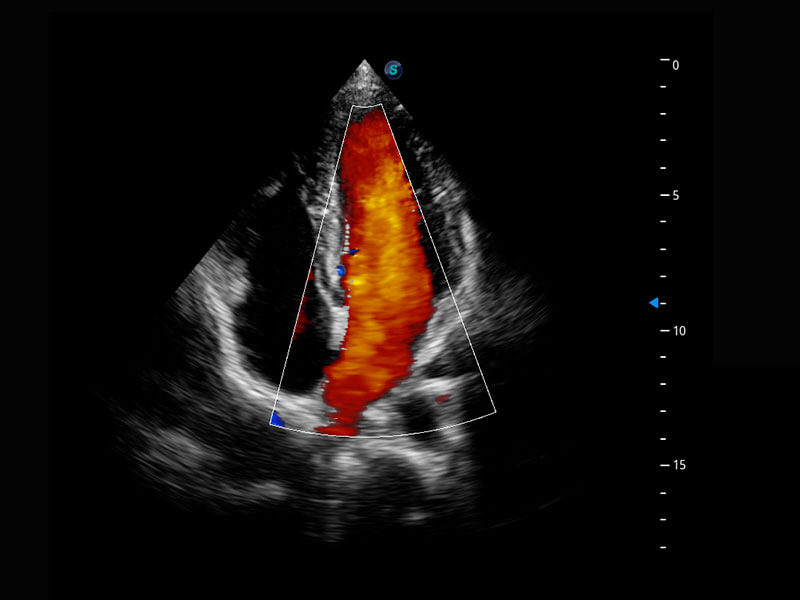

P60搭载一系列胎儿心脏成像技术,实现精细的胎儿心脏评估。

四腔心血流